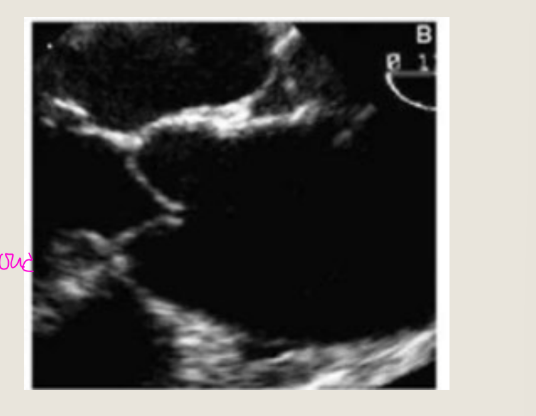

VSD with Aortic Prolapse

in diastole

This is best evaluated in what view

In diastole (right), the intra-aortic pressure

forces the aortic valve leaflet to close, but

the unsupported right coronary cusp is

pushed down into the left ventricular

outflow tract away from the opposed

coronary cusp, resulting in regurgitation

This is best evaluated in PLAX